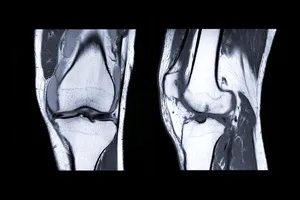

무릎 인공관절수술은 심각하게 손상된 무릎 관절을 인공 관절로 대체하는 수술입니다. 퇴행성 관절염, 외상성 관절염 등으로 인해 무릎 통증이 심하고, 일상생활에 지장을 초래하는 경우, 인공관절 수술을 통해 통증을 완화하고 운동 기능을 회복할 수 있습니다.

또한, 무릎 관절이 심하게 변형되어 다리가 O 또는 X 형태가 되는 경우, 뼈와 뼈가 서로 마찰하는 모습이 보이는 경우도 고려할 수 있습니다.